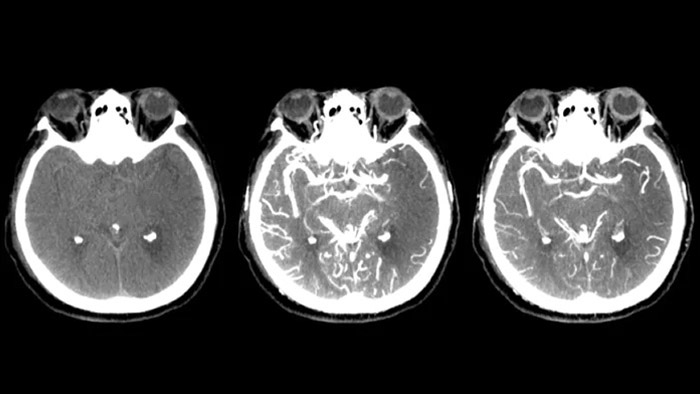

Tres SmartCT

Visualización similar a la de un TAC

SmartCT Soft Tissue  genera una visualización similar a la de un TAC convencional de tejido blando y respalda el diagnóstico de accidentes cerebrovasculares de tres maneras. Una exploración sin contraste ayuda a la detección de cambios isquémicos tempranos. Una exploración en fase temprana ayuda a identificar la oclusión proximal. Una exploración con contraste en fase tardía respalda la detección de colaterales.

Ver la repleción colateral

Visualización de la repleción colateral

Dual View permite visualizar  los volúmenes de TAC de haz cónico de fase temprana y tardía yuxtapuestos mejorando la identificación de penumbra y la visualización de la repleción colateral.